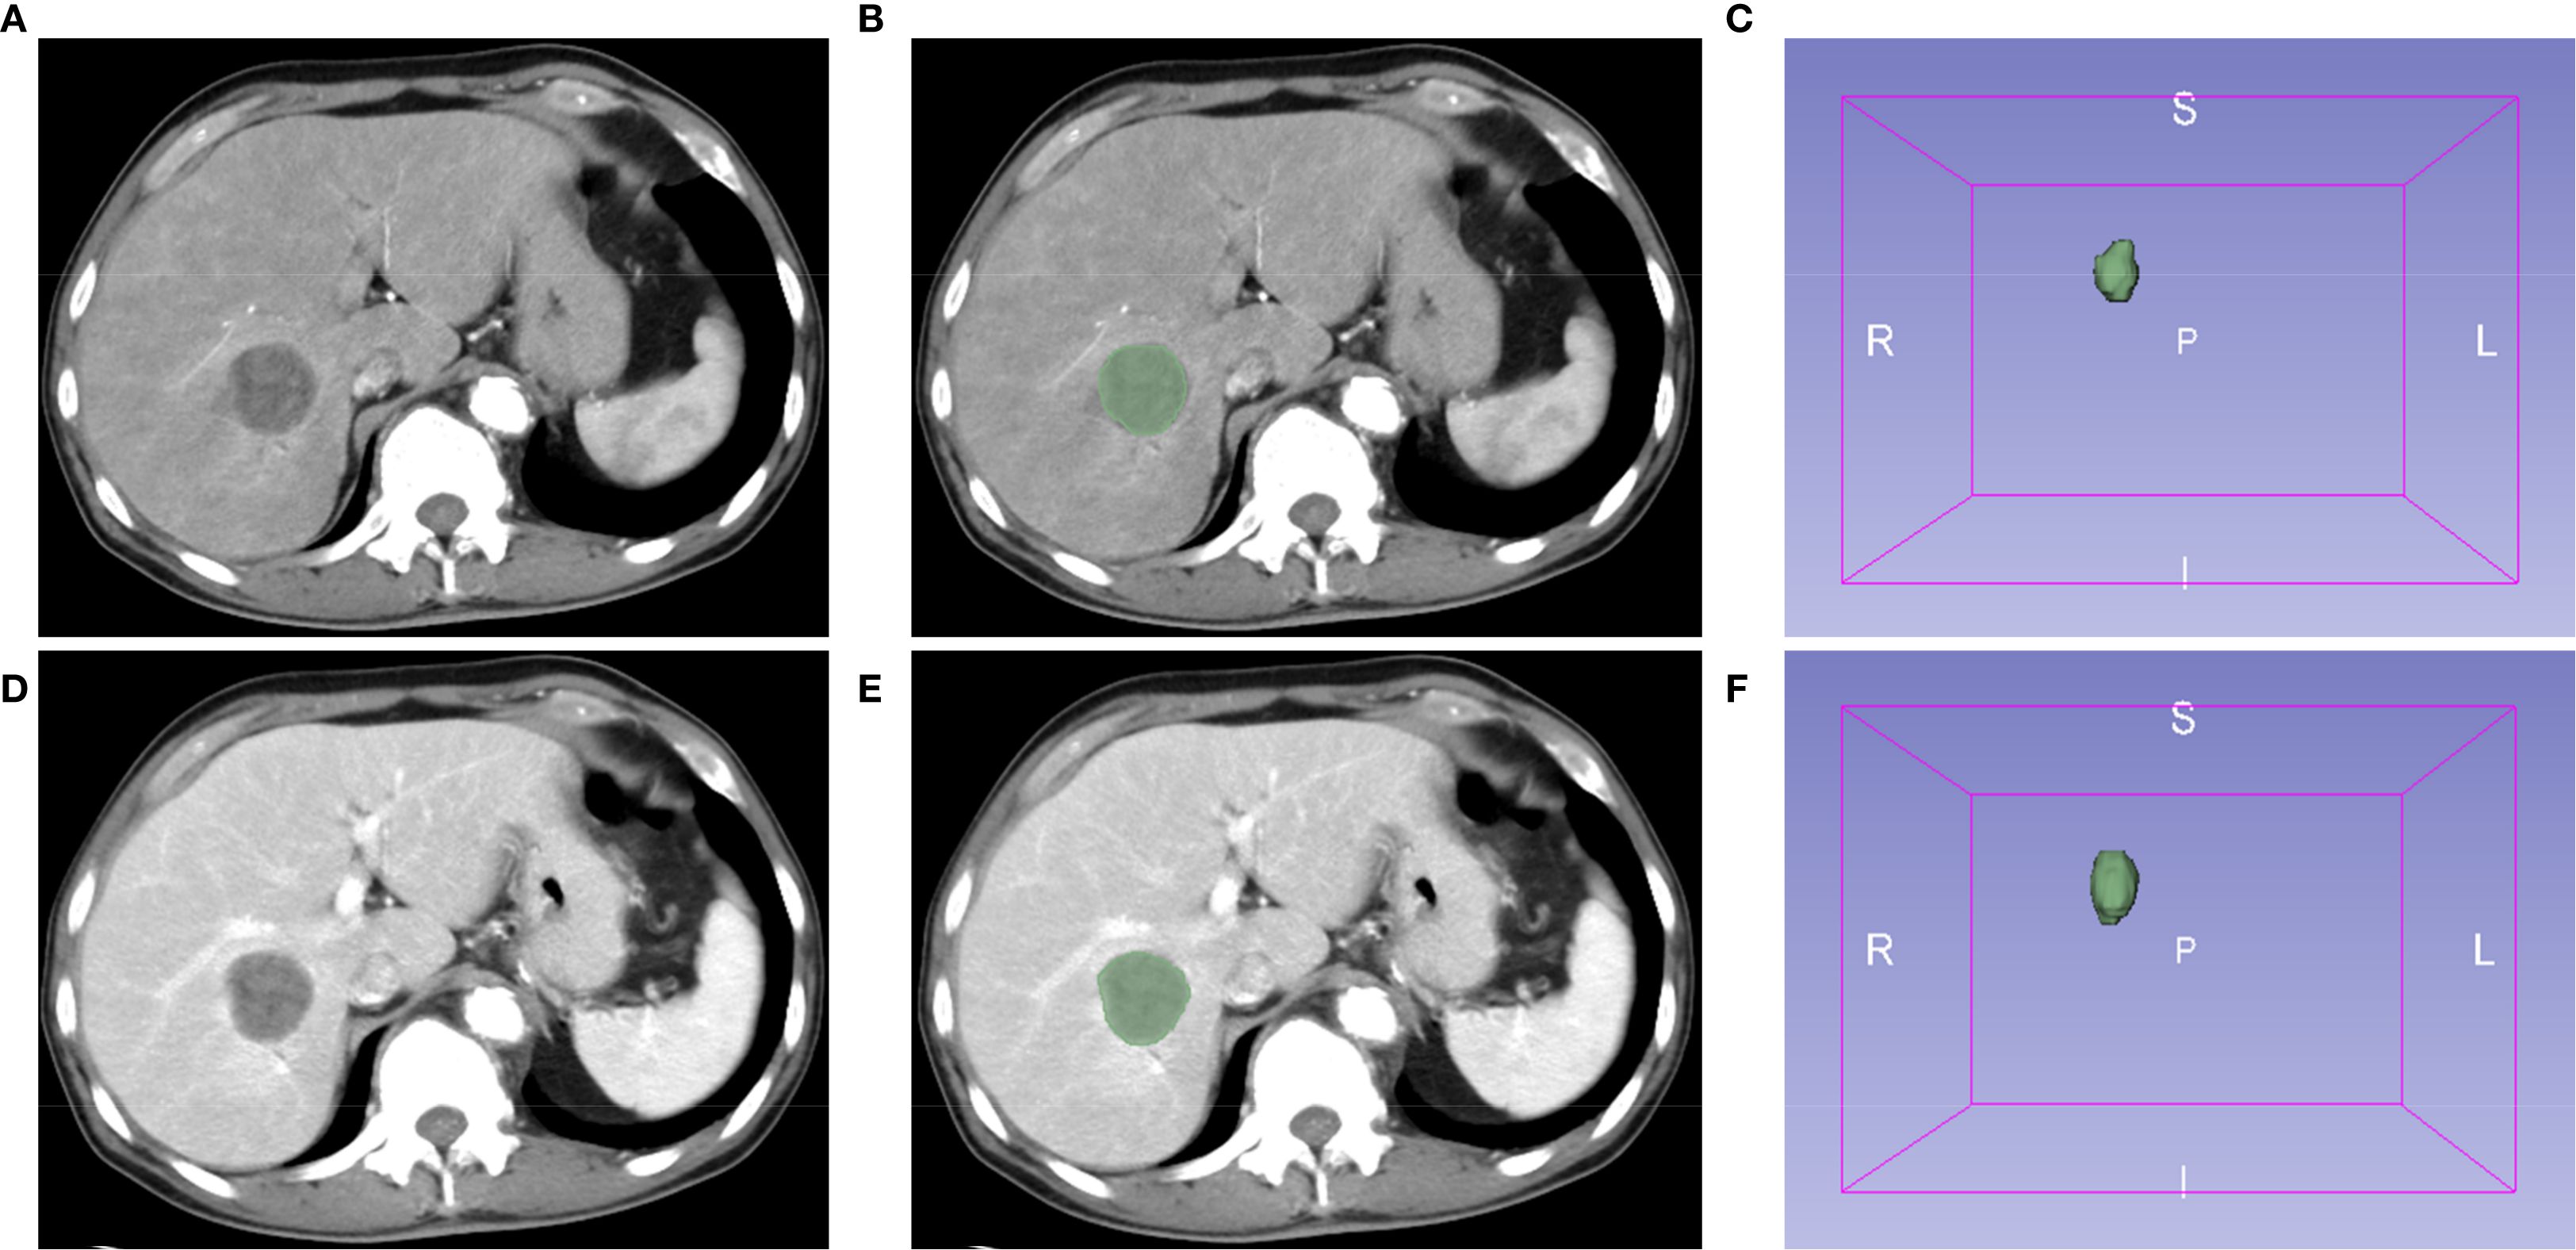

Images of contrast-enhanced CT arterial and venous phases of included patients were exported in the DICOM format. Two authors (CLZ and XLX) manually segmented tumors and outlined regions of interest (ROI) on each layer of images using the Segment Editor module of 3D Slicer software (version 5.4.0) (Figure 1). Images were resampled into voxels of 1×1×1 mm3 size using the SimpleITK module (version 2.3.1) in Python (version 3.9.12) to standardize voxel spacing. By default, B-Spline interpolation (order = 3) was applied for image resampling, while Nearest-Neighbor interpolation (order = 1) was used for ROI masks to preserve segmentation boundaries. The Python-based PyWavelets (version 1.3.0) package was used to perform wavelet transforms on all contrast-enhanced CT sequences to reduce image noise and normalize intensities. Finally, the PyRadiomics (version 3.1.0) package was used to extract 1,316 radiomics features from seven image types for each ROI, including shape features, first-order intensity features, and higher-order texture features derived from available filters (e.g., wavelet, Laplacian of Gaussian [LoG], and square) (17).

Figure 1. Extraction of radiomics features using the 3D Slicer software. Representative images of contrast-enhanced computed tomography (CT) arterial (A) and venous (D) phases. (B, E) Regions of interest (ROI). (C, F) The 3D reconstruction of tumors.